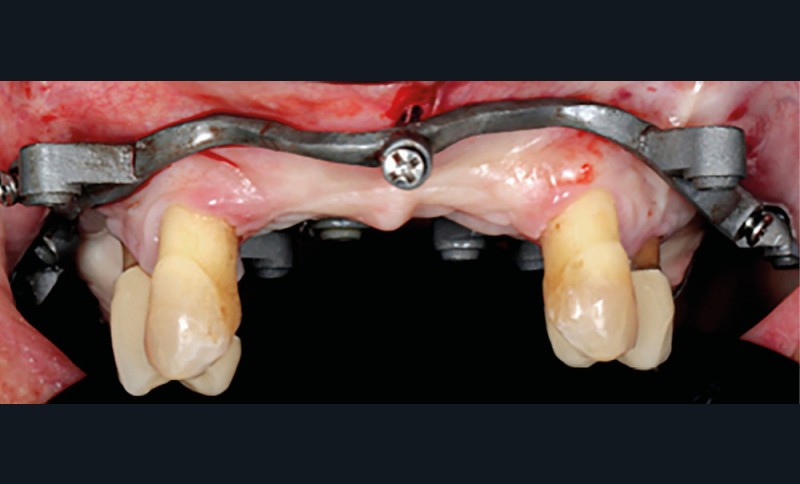

La première étape du protocole des guides à étages (Your3DGuide) est la connexion du guide de positionnement à appui dentaire à la base crâniale métallique hors de la bouche (fig. 4). Cette dernière sera fixée à l’aide de vis transmuqueuses vestibulaires et palatines (fig. 5). Nous avons choisi ce système car la base titane est frittée par laser, ce qui lui conférerait une précision d’adaptation et une rigidité supérieure à une base résine tout en conservant une faible épaisseur. Sur cette base vont se visser les autres étages assurant une stabilisation et évitant un éventuel mouvement lors du forage (et lors de la solidarisation du provisoire).